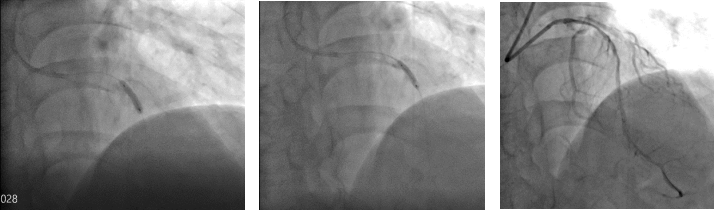

切割扩张后

考虑到目前传统“冠脉内旋磨技术”无法有效解决冠脉深层钙化病变,仔细评估患者病情与适应症后,楚天舒主任当机立断决定使用“Shockwave IVL”新技术处理复杂钙化病变。

冲击波球